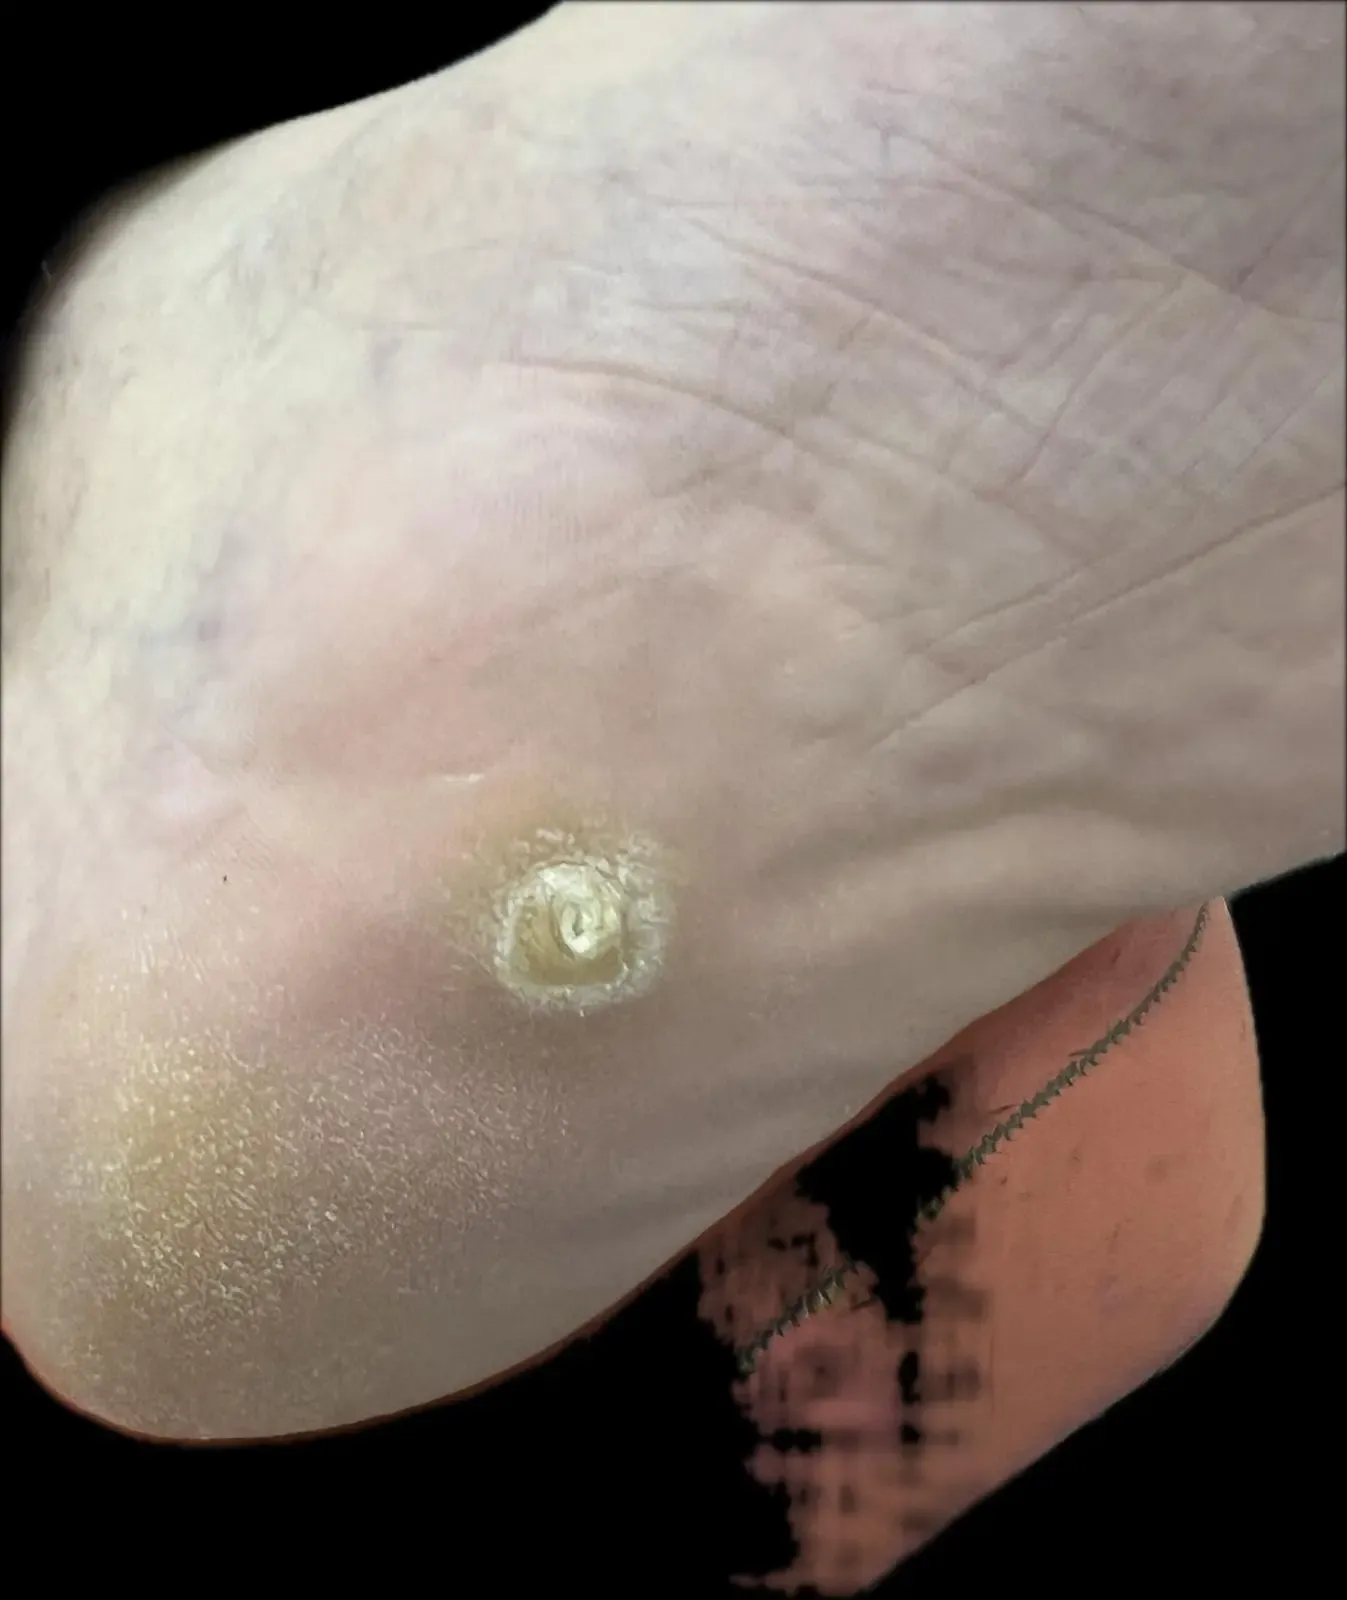

Figura 5: Detalle de la lesión hiperqueratósica que causa dolor intenso tipo ‘clavo’ al caminar.